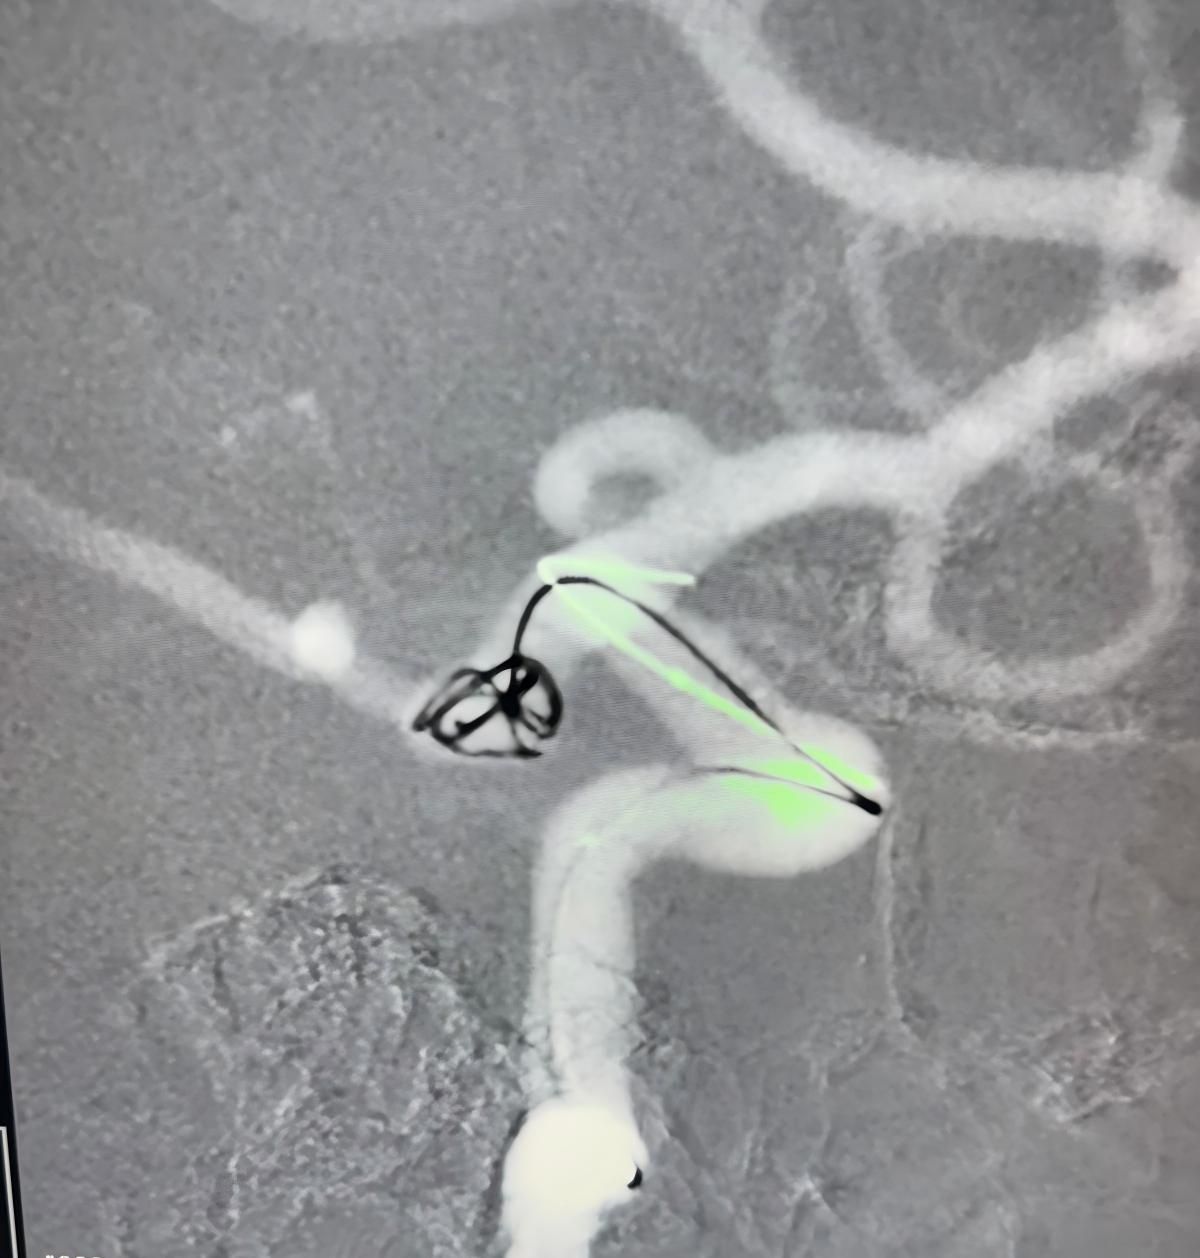

Temos o prazer de compartilhar um recente procedimento bem sucedido na Clínica Alma Mater, Medellín, realizado pelo Dr. Jorge Mutis.

O tratamento utilizou a Nuva®Desvio de fluxo (TJED-D 5.0-14), Perdenser®Bobina 3D, e Frepass®Microcateter (TJMC18 Plus) para aneurisma da artéria comunicante posterior.

O Dr. Mutis destacou a excelente visibilidade do dispositivo e observou que a recuperação foi suave. Ele expressou grande satisfação com o resultado final.